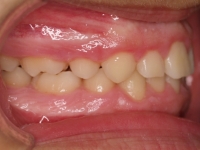

El paciente M.C. acude a nuestra consulta por:

– Apiñamiento importante

– Perfil convexo

– Forma arcada estrecha

-sobremordida

Con lo que decide realizarse un tratamiento de ortodoncia de duración de 26 meses con brackets smartclip 022 de acero.

Fotos antes tratamiento: